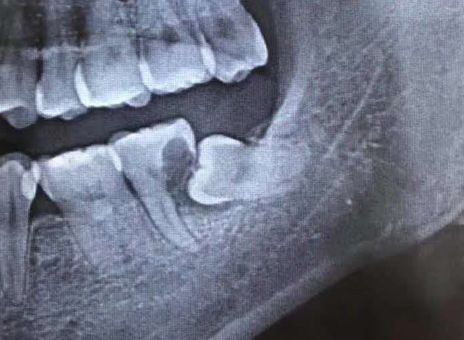

患者张先生2个月前突然发现,自己下颌左侧牙齿,遇凉、热都会剧烈疼痛,甚至不敢用左侧牙齿吃东西,在某口腔门诊钻开牙齿,反复换药治疗几次后仍未见缓解,才想着到大医院看一看。二一五医院口腔科接诊后发现,患者口内下颌最后一颗牙齿上有溢出的白色充填材料,而这颗患牙在几次不当治疗后,已经明显松动,且咬合时剧烈疼痛,患者自述在前期治疗过程中没拍X线片明确病情,接诊医师随即为他安排了口腔CT拍摄。CT发现,在这“摇摇欲坠”的牙齿下,还悄悄隐藏着一颗倾斜的智齿,而这颗智齿,已经几乎“吃光了”它侧方“松动”牙齿的牙根,这才是导致张先生牙疼反复治疗无效的根本原因!